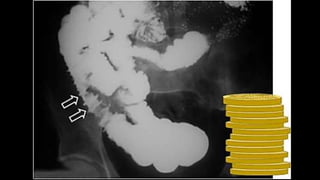

SIGNO DE LA PILA DE MONEDAS

• Aspecto de los pliegues intestinales engrosados, lisos, rectos

y perpendiculares al eje longitudinal.

• El signo se presenta cuando existe infiltración difusa de la

submucosa por edema o hemorragia intramural

(traumatismo, isquemia, toma de anticoagulantes, etc.)

• Más evidente en yeyuno por el mayor tamaño de los

pliegues

SIGNO DE LAPILA DE MONEDAS • Aspecto de los pliegues intestinales engrosados, lisos, rectos y perpendiculares al eje longitudinal. • El signo se presenta cuando existe infiltración difusa de la submucosa por edema o hemorragia intramural (traumatismo, isquemia, toma de anticoagulantes, etc.) • Más evidente en yeyuno por el mayor tamaño de los pliegues